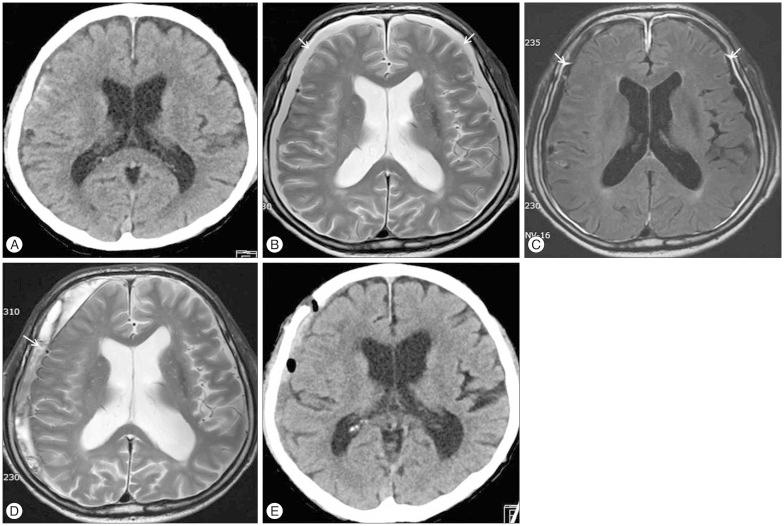

Thirty-one patients suffered from bilateral SDG, whereas 14 had unilateral SDG. Follow-up computed tomography scans revealed regression of SDG in 25 of 45 patients (55.6%), but the remaining 20 patients (44.4%) suffered from transition to CSDH. Eight patients developed bilateral CSDH, and 12 patients developed unilateral CSDH. Hemorrhage-free survival rates were significantly lower in the male and bilateral SDG group (log-rank test; =0.043 and =0.013, respectively). Binary logistic regression analysis revealed male (OR, 7.68; 95% CI 1.18-49.78; =0.033) and bilateral SDG (OR, 8.04; 95% CI 1.41-45.7; =0.019) were significant risk factors for development of CSDH.

31例患者患有双侧SDG,而14例患有单侧SDG。随访计算机断层扫描显示,45例患者中有25例(55.6%)的SDG消退,但其余20例患者(44.4%)转变为CSDH。8例患者发生双侧CSDH,12例患者发生单侧CSDH。男性和双侧SDG组的无出血生存率显著较低(对数秩检验;分别为=0.043和=0.013)。二元逻辑回归分析显示,男性(比值比,7.68;95%置信区间1.18-49.78;=0.033)和双侧SDG(比值比,8.04;95%置信区间1.41-45.7;=0.019)是CSDH发生的显著危险因素。